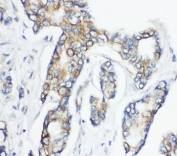

IHC-P: CD1d antibody testing of human breast cancer tissue

IHC (FFPE) : 0.5-1ug/ml